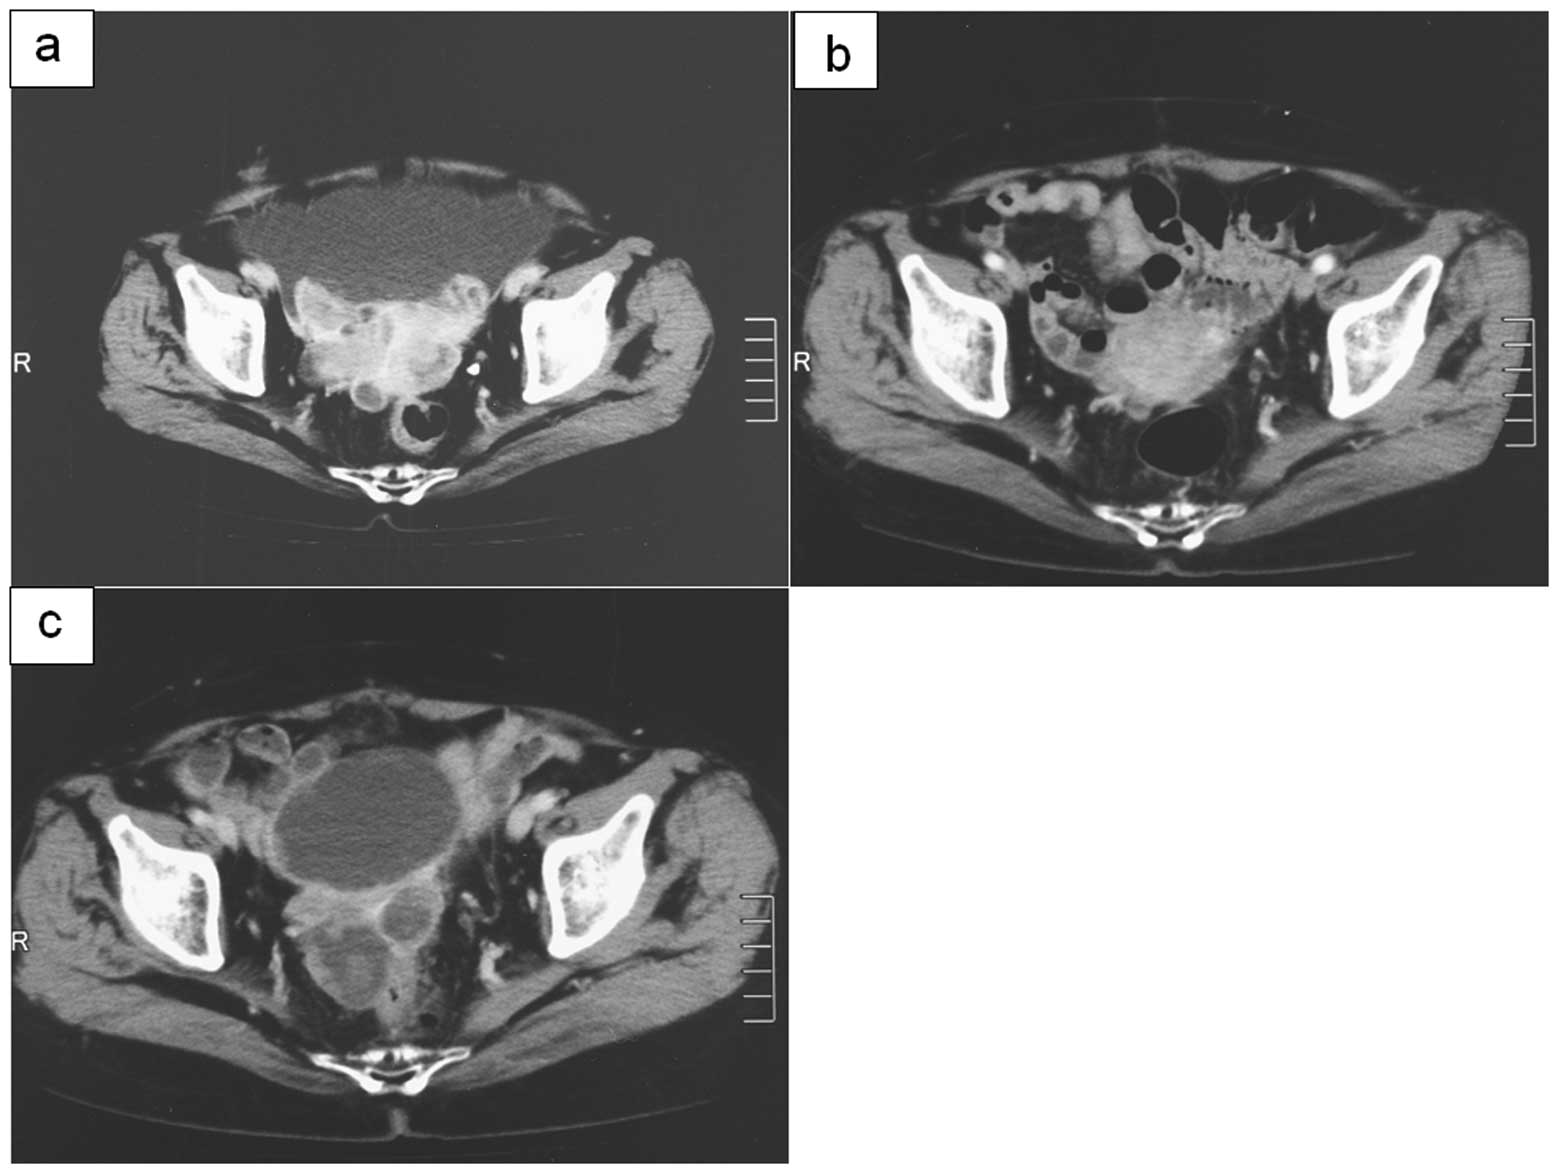

The utility of serum N-ERC/mesothelin as a biomarker of ovarian carcinoma

Ovarian carcinoma has been difficult to diagnose at an early stage. Recently, it has been recognized that the measurement of blood N-ERC/mesothelin levels aids early detection in and postoperative therapeutic monitoring of patients with mesothelioma, who have been exposed to asbestos. ERC/mesothelin has also been reported to be expressed in ovarian carcinoma. We determined serum N-ERC/mesothelin levels in patients with ovarian carcinoma using an enzyme‑linked immunosorbent assay (ELISA). In addition, we immunohistochemically evaluated surgically resected specimens for C-ERC/mesothelin expression. As a result, of the 32 patients with ovarian tumors (18 carcinoma, 2 borderline tumors), one patient with serous adenocarcinoma showed increased N-ERC/mesothelin levels. Immunohistochemically, of the 20 ovarian tumor (carcinoma and borderline tumor) specimens evaluated for serum N-ERC/mesothelin, 9 (45.0%) were positive for C-ERC/mesothelin. The C-ERC/mesothelin-positive specimens were found to be serous and clear cell adenocarcinomas. If serum N-ERC/mesothelin, which is considered useful for early detection in and therapeutic monitoring of patients with mesothelioma, may also be used for ovarian carcinoma monitoring, it may be a valuable serum tumor marker for the early detection of ovarian carcinoma.

Figure 1

Figure 2

Figure 3

Figure 4